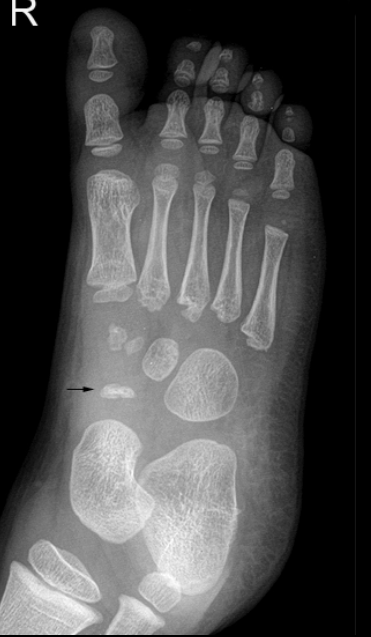

What bone is affected in Köhler’s disease?

Navicular bone (foot).

Typical age group for Köhler’s disease?

Children 3–7, mainly boys.

Signs & symptoms of Köhler’s disease?

Midfoot pain/swelling, limping with weight shifted laterally.

Radiographic findings in Köhler’s disease?

Patchy/homogeneous sclerosis, collapse/fragmentation, eventual revascularization with abnormal shape.

Treatments for Köhler’s disease?

Pain relief, 6–8 weeks casting, arch supports; resolves with time.